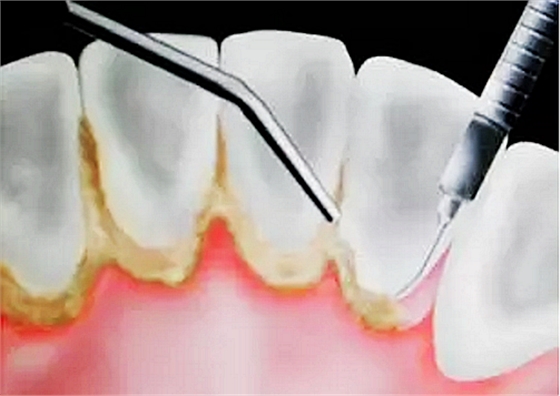

當牙齦下存在的牙結石,或有牙槽骨吸收跡象時,常規(guī)潔牙往往無法清除牙齦下的結石,此時需要進行牙周刮治了。

![U7FZD~BYN9(C]S_P$Q_V)4R.png U7FZD~BYN9(C]S_P$Q_V)4R.png](/Mobile/UploadFiles/FCK/2017-06/6363253152156700223823897.png_280.jpg)

牙槽骨一旦吸收很難再生,所以,牙周刮治的目的是為了防止進一步的牙槽骨吸收,牙周袋形成以及牙齦出血。更有利于牙齒的穩(wěn)固和健康。